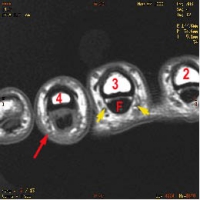

L'étude des ruptures des poulies peut se faire à l'aide d'examens complémentaires (échographie, scanner ou IRM). L'imagerie est réalisée, les doigts en extension puis en flexion contrariée ++

- signe indirect : en flexion contrariée, le tendon fléchisseur s'éloigne de la corticale phalangienne palmaire et "prend la corde"

la poulie A2 et rompue, lorsque le fléchisseur s'éloigne de la premiére phalange

la poulie A4 est lésée lorsque le fléchisseur s'éloigne de la phalange intermédiaire